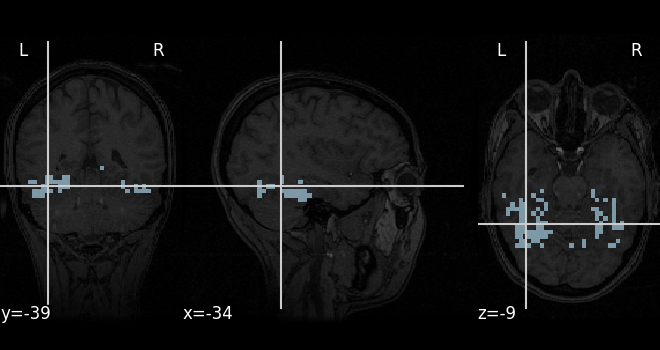

Searchlight analysis of face vs house recognition

Fit a classifier a large amount of times in order to distinguish between face- and house-related cortical areas.